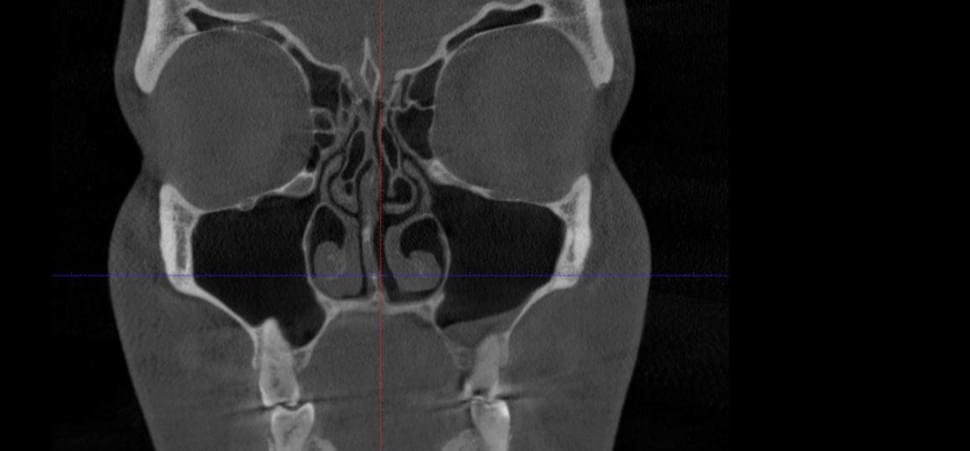

Це «золотий стандарт» діагностики для ЛОР-лікарів та щелепно-лицевих хірургів. Дослідження дозволяє отримати детальну 3D-модель усіх повітроносних порожнин черепа: гайморових, лобних, клиновидних пазух та решітчастого лабіринту. На відміну від звичайного рентгену, КТ показує не просто наявність запалення, а його точну локалізацію, причину та структуру.

✅ Що побачить лікар на КТ двох щелеп?

🔹 "Зубний" гайморит: Чи є корінь зуба причиною запалення в пазусі (одонтогенний гайморит)? Це

часто трапляється, коли корені верхніх зубів проростають у дно гайморової пазухи.

🔹 Приховані патології: Наявність кіст, поліпів, сторонніх тіл (наприклад, пломбувальний

матеріал, що потрапив у пазуху) або грибкових тіл.

🔹 Анатомія носа: Ступінь викривлення носової перегородки та стан носових раковин (гіпертрофія

слизової).

🔹 Заповненість пазух: Рівень рідини чи гною, потовщення слизової оболонки.

🔹 Травми: Тріщини або переломи стінок носа та орбіт.